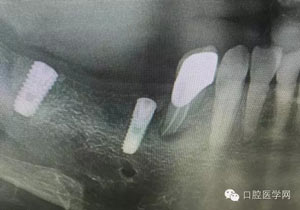

病例1:患者迫切希望保留自己的這一顆牙齒,根尖周陰影比較大,二度松動(dòng).而且旁邊有種植修復(fù)體,和患者溝通好后,治療好后觀察一個(gè)月后冠修復(fù),因?yàn)橛蟹N植的后期修復(fù),所以有了機(jī)會(huì)觀察,術(shù)后三個(gè)月和術(shù)后四個(gè)月,根尖恢復(fù)的還算不錯(cuò),希望能夠繼續(xù)觀察下去.這樣子的病例,做的時(shí)候我們一定要非常的小心,和患者要有充分的溝通以及不同科室的溝通然后決定怎么樣做比較好,假如就是出現(xiàn)了問(wèn)題,到時(shí)候我們也比較好處理些,免得我們自己到時(shí)候不好收?qǐng)觥?/span>